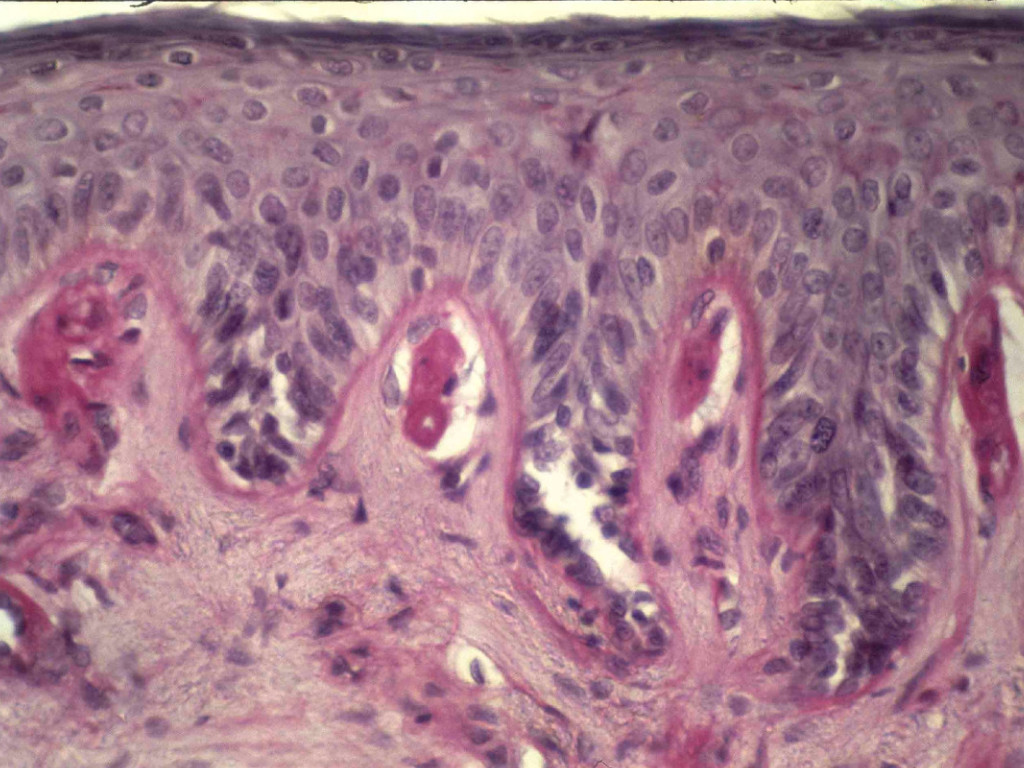

Histologisch onderzoek bij EP: vacuolisatie van epidermale cellen wordt gezien in acute laesies, intercellulair oedeem als vacuolisatie en lysis van endotheliale cellen in de superficiele dermale bloedvaten. In oudere laesies wordt eosinofiele pas-positieve deposities rondom de bloedvaten gezien, tevens verdikking en degeneratie van de capillaire basale membraan.

Erythropoietische protoporfyrie Histologie (immunofluorescentie) porphyria cutanea tarda

PAS positieve deposities IgG rond vaten

IF-Foto: www.dermatlas.net.